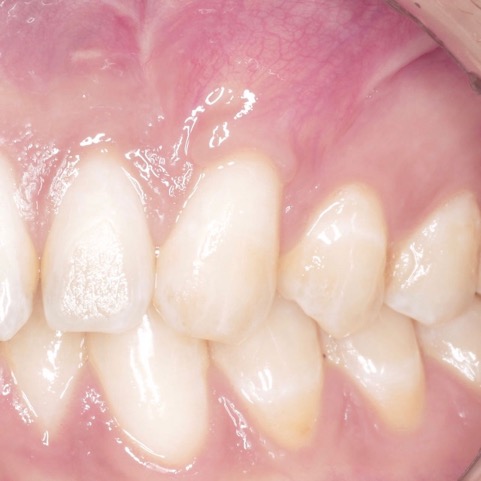

TERAPIA DELLE RECESSIONI GENGIVALI

La terapia delle recessioni gengivali consiste nel ricostituire i tessuti gengivali perduti per ricoprire le radici esposte dei denti e restituire un’adeguata estetica al sorriso.

La procedura prevede un prelievo di tessuto connettivo dal palato, il trattamento della radice esposta, la preparazione dell’innesto e la sua collocazione nel sito ricevente.